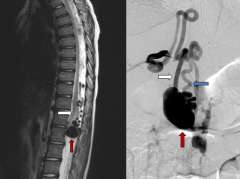

• CT scan of Type IV Pial Spinal Arteriovenous Fistula

Figure 2. Type IV Pial Spinal Arteriovenous Fistula – sagittal or side view of a T2 MRI of the spine (left) showing a massively enlarged spinal vein (red arrow) compressing the spinal cord (white arrow).

Pial Spinal Arteriovenous Fistulas (Type IV)

• Pial spinal AFVs are a direct connection between an artery and a vein on the surface of the spinal cord. These lesions are very rare and come to attention for various reasons, such as when the vein has become enlarged due to high pressure from the artery and this structure begins to compress the spinal cord (Figure 2).